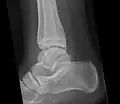

Ankle

Accessory bones of the ankle.[13]

Accessory bones at the ankle mainly include:

• Os subtibiale, with a prevalence of approximately 1%.[14] It is a secondary ossification center of the distal tibia that appears during the first year of life, and which in most people fuses with the shaft at approximately 15 years in females and approximately 17 years in males.[14]

• Os subfibulare, with a prevalence of approximately 0.2%.[15]

Os trigonum (further described below) may also be seen on an ankle X-ray.